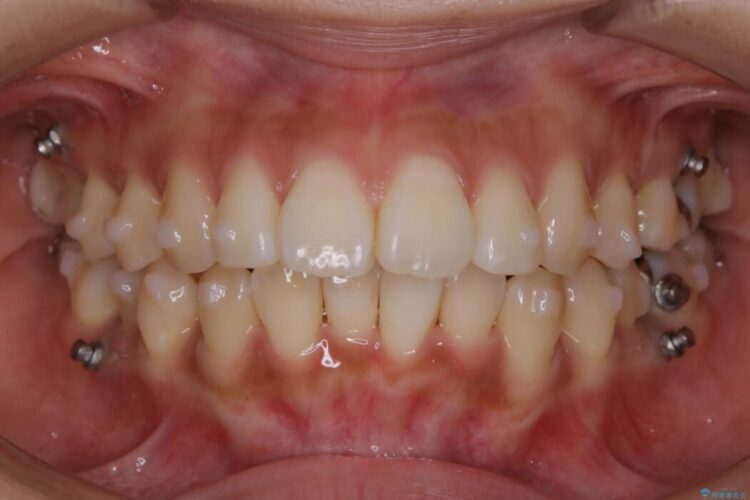

- 矯正装置:インビザライン+マイクロインプラント

患者様からなおしたい内容をお聞きしたところ

・上下の歯のガタつき

・出っ歯感(口ゴボ)

・噛み合わせ

よって患者様ご希望の非抜歯かつマウスピースでの矯正を行うために、最大量の臼歯の遠心移動をして歯列全体を奥へ引っ込める計画をご提案しました。

非抜歯での矯正治療

マウスピースにマイクロインプラントという補助装置を併用することで抜歯をせずとも歯列を整えるスペースを確保することができます。奥歯から順に移動させていくので前歯に変化が出るまでには時間がかかってしまいますが、健康な歯を抜歯することなく理想的な歯並びを手に入れることができます。